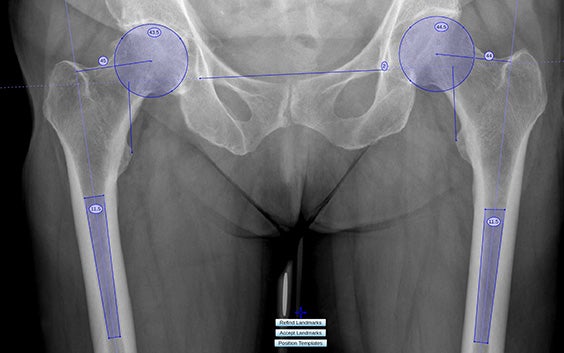

Analyse bilatérale intelligente de la hanche

Réalisez facilement une évaluation complète des deux hanches grâce à l'analyse bilatérale intelligente, qui intègre des mesures controlatérales (décalage acétabulaire et fémoral) pour recréer la biomécanique naturelle